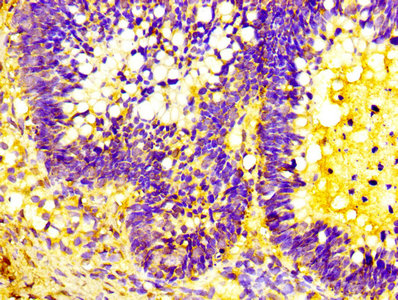

Immunohistochemistry analysis of human cervical cancer using CSB-PA10599A0Rb at dilution of 1:100